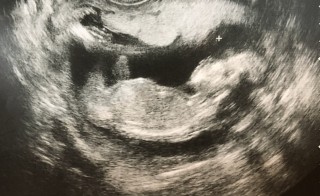

戌の日参りの帰りに検診へ。手で頭を掻いたり振り回したり、元気に動いてました!顔が旦那に似ていて、一緒に居た旦那が嬉しそうに笑ってました。男の子っぽかったけど、まだわからないとのこと。次回が楽しみです。すくすく育ってね♡